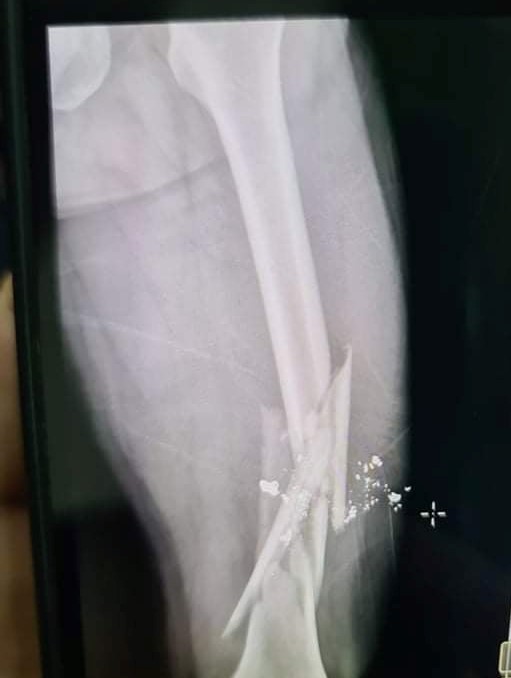

| Hình ảnh xương đùi của G. bị gãy |

Sau cuộc nhậu, do bức xúc vì bị đấm, Phan Công H. đã dùng súng bắn anh G. gãy xương đùi. Ngay sau đó anh G. được mọi người xung quanh đưa đến bệnh viện cấp cứu.